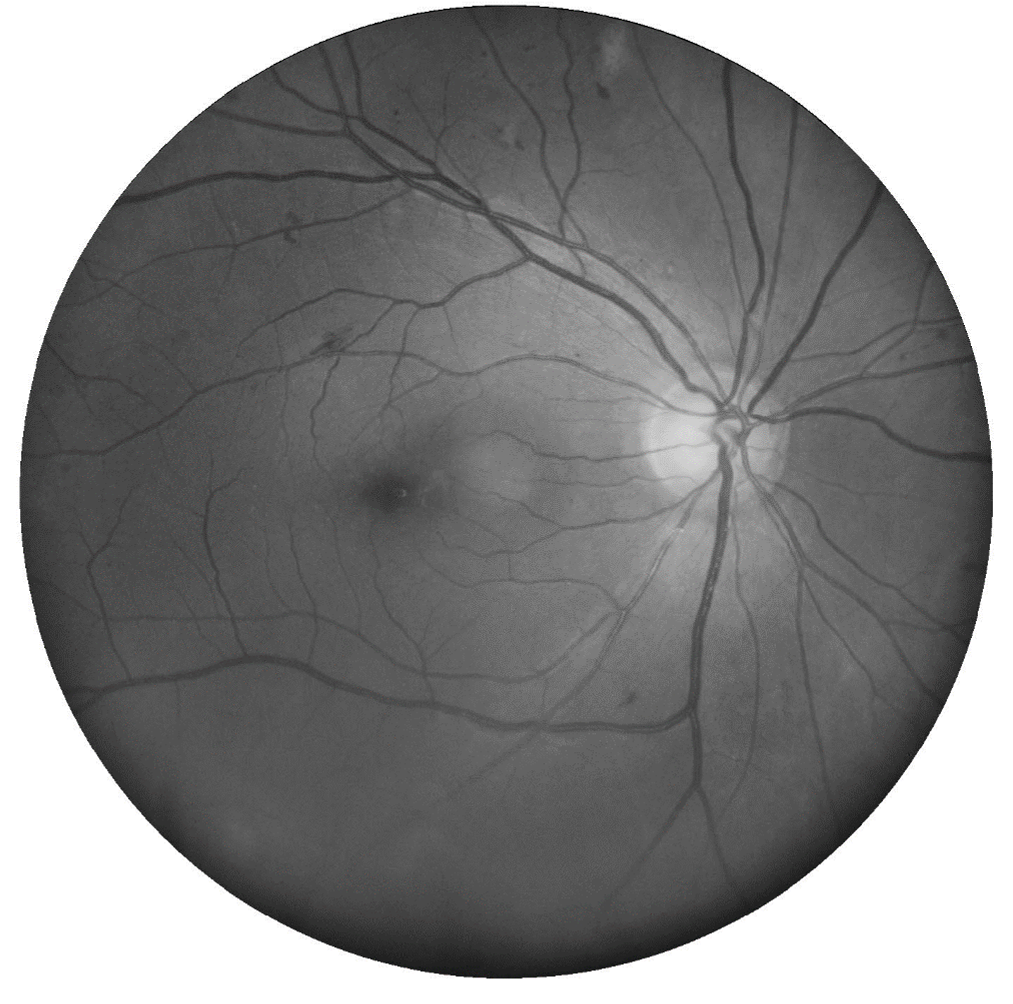

Lesions of Non-Proliferative Diabetic Retinopathy

Microaneurysms

Microaneurysms are the earliest clinical sign of DR. They are outpouchings of the capillary wall, due to pericyte loss, which can rupture and leak leading to intraretinal haemorrhage, oedema or hard exudate.

Clinically, they appear as isolated, round red dots of varying size which can resolve spontaneously. They may be undetectable on OCT or, if visible, typically appear as small round or oval lesions, originating from either the superficial or deep capillary plexi , fully or partially capsulated in 56% of cases.

Dot and blot haemorrhages

Dot and blot haemorrhages are usually caused by a ruptured or leaking microaneurysm or retinal capillary, typically within the inner nuclear layer (INL) or outer plexiform layer (OPL).

Dot haemorrhages lie deeper in the retina than blot haemorrhages and can be difficult to distinguish from microaneurysms. Dot/blot haemorrhages take longer to resolve than more superficial flame-shaped haemorrhages.

Cotton wool spot

Cotton wool spots result arise from retinal ischaemia in diabetic retinopathy, however other factors responsible for focal disruption of axoplasmic flow in the retinal nerve fibre layer may result in a similar presentation.

They appear as slightly elevated, yellow-white or grey-white, cloud-like lesions, are typically found in the posterior pole and less than 1/3 disc diameter in size.

Venous beading

Venous beading is a venous calibre irregularity which occurs in areas of severe retinal hypoxia. A sausage-link appearance occurs in severe cases. Other vascular remodelling occurs in diabetic retinopathy such as dilation, reduplication and loops.

Intraretinal microvascular anomalies (IRMA)

Intraretinal microvascular abnormalities (IRMA) are abnormal intraretinal shunts which appear as branching or dilation of capillaries within the retina in areas of poor retinal perfusion. They have a similar appearance to NV but with slightly larger vessel calibre. They are a precursor to NV which may form in close proximity.